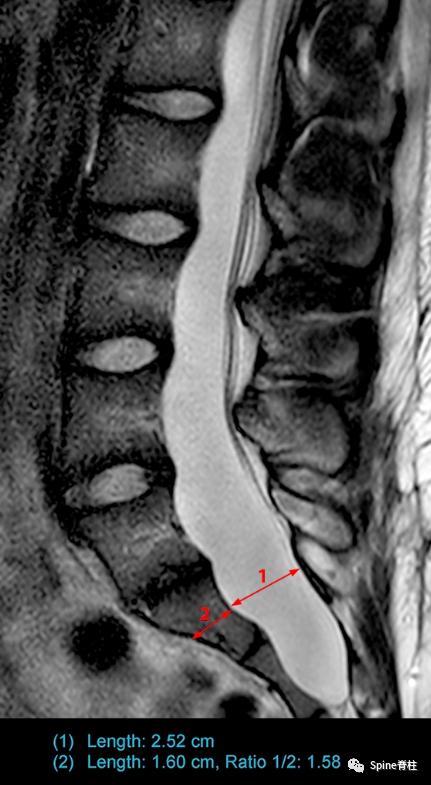

一个马凡综合征伴硬膜扩张患者的MRI。a为T2正中矢状位提示S2硬膜囊的宽度大于L4,存在骶骨前硬膜膨出,S1的扇形缺损值为5.1。c为横断面提示一个神经根袖直径>7.0mm。因此,这个患者满足两个主要标准和两个次要标准。